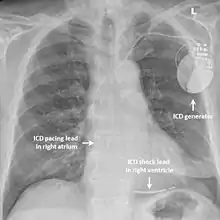

| Treatment | Medication, implantable cardioverter-defibrillator |

Arrhythmias

As in other forms of long QT syndrome which predispose those affected to dangerous heart rhythm disturbances, the risk of arrhythmias can be reduced by taking beta blockers such as propranolol that block the effects of adrenaline on the heart.[3] Other antiarrhythmic drugs such as flecainide and verapamil may also be helpful.[3] Those at highest risk of recurrent arrhythmias such as those who have already suffered a cardiac arrest may benefit from an implantable cardioverter defibrillator – a small device implanted under the skin which can detect dangerous arrhythmias and automatically treat them with a small electric shock.[3]